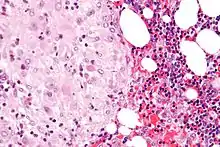

The decidua has a histologically-distinct appearance, displaying large polygonal decidual cells in the stroma. These are enlarged endometrial stromal cells, which resemble epithelium (and are referred to as "epithelioid").

- Acute choriodeciduitis, with neutrophils seen in the chorion and decidua.